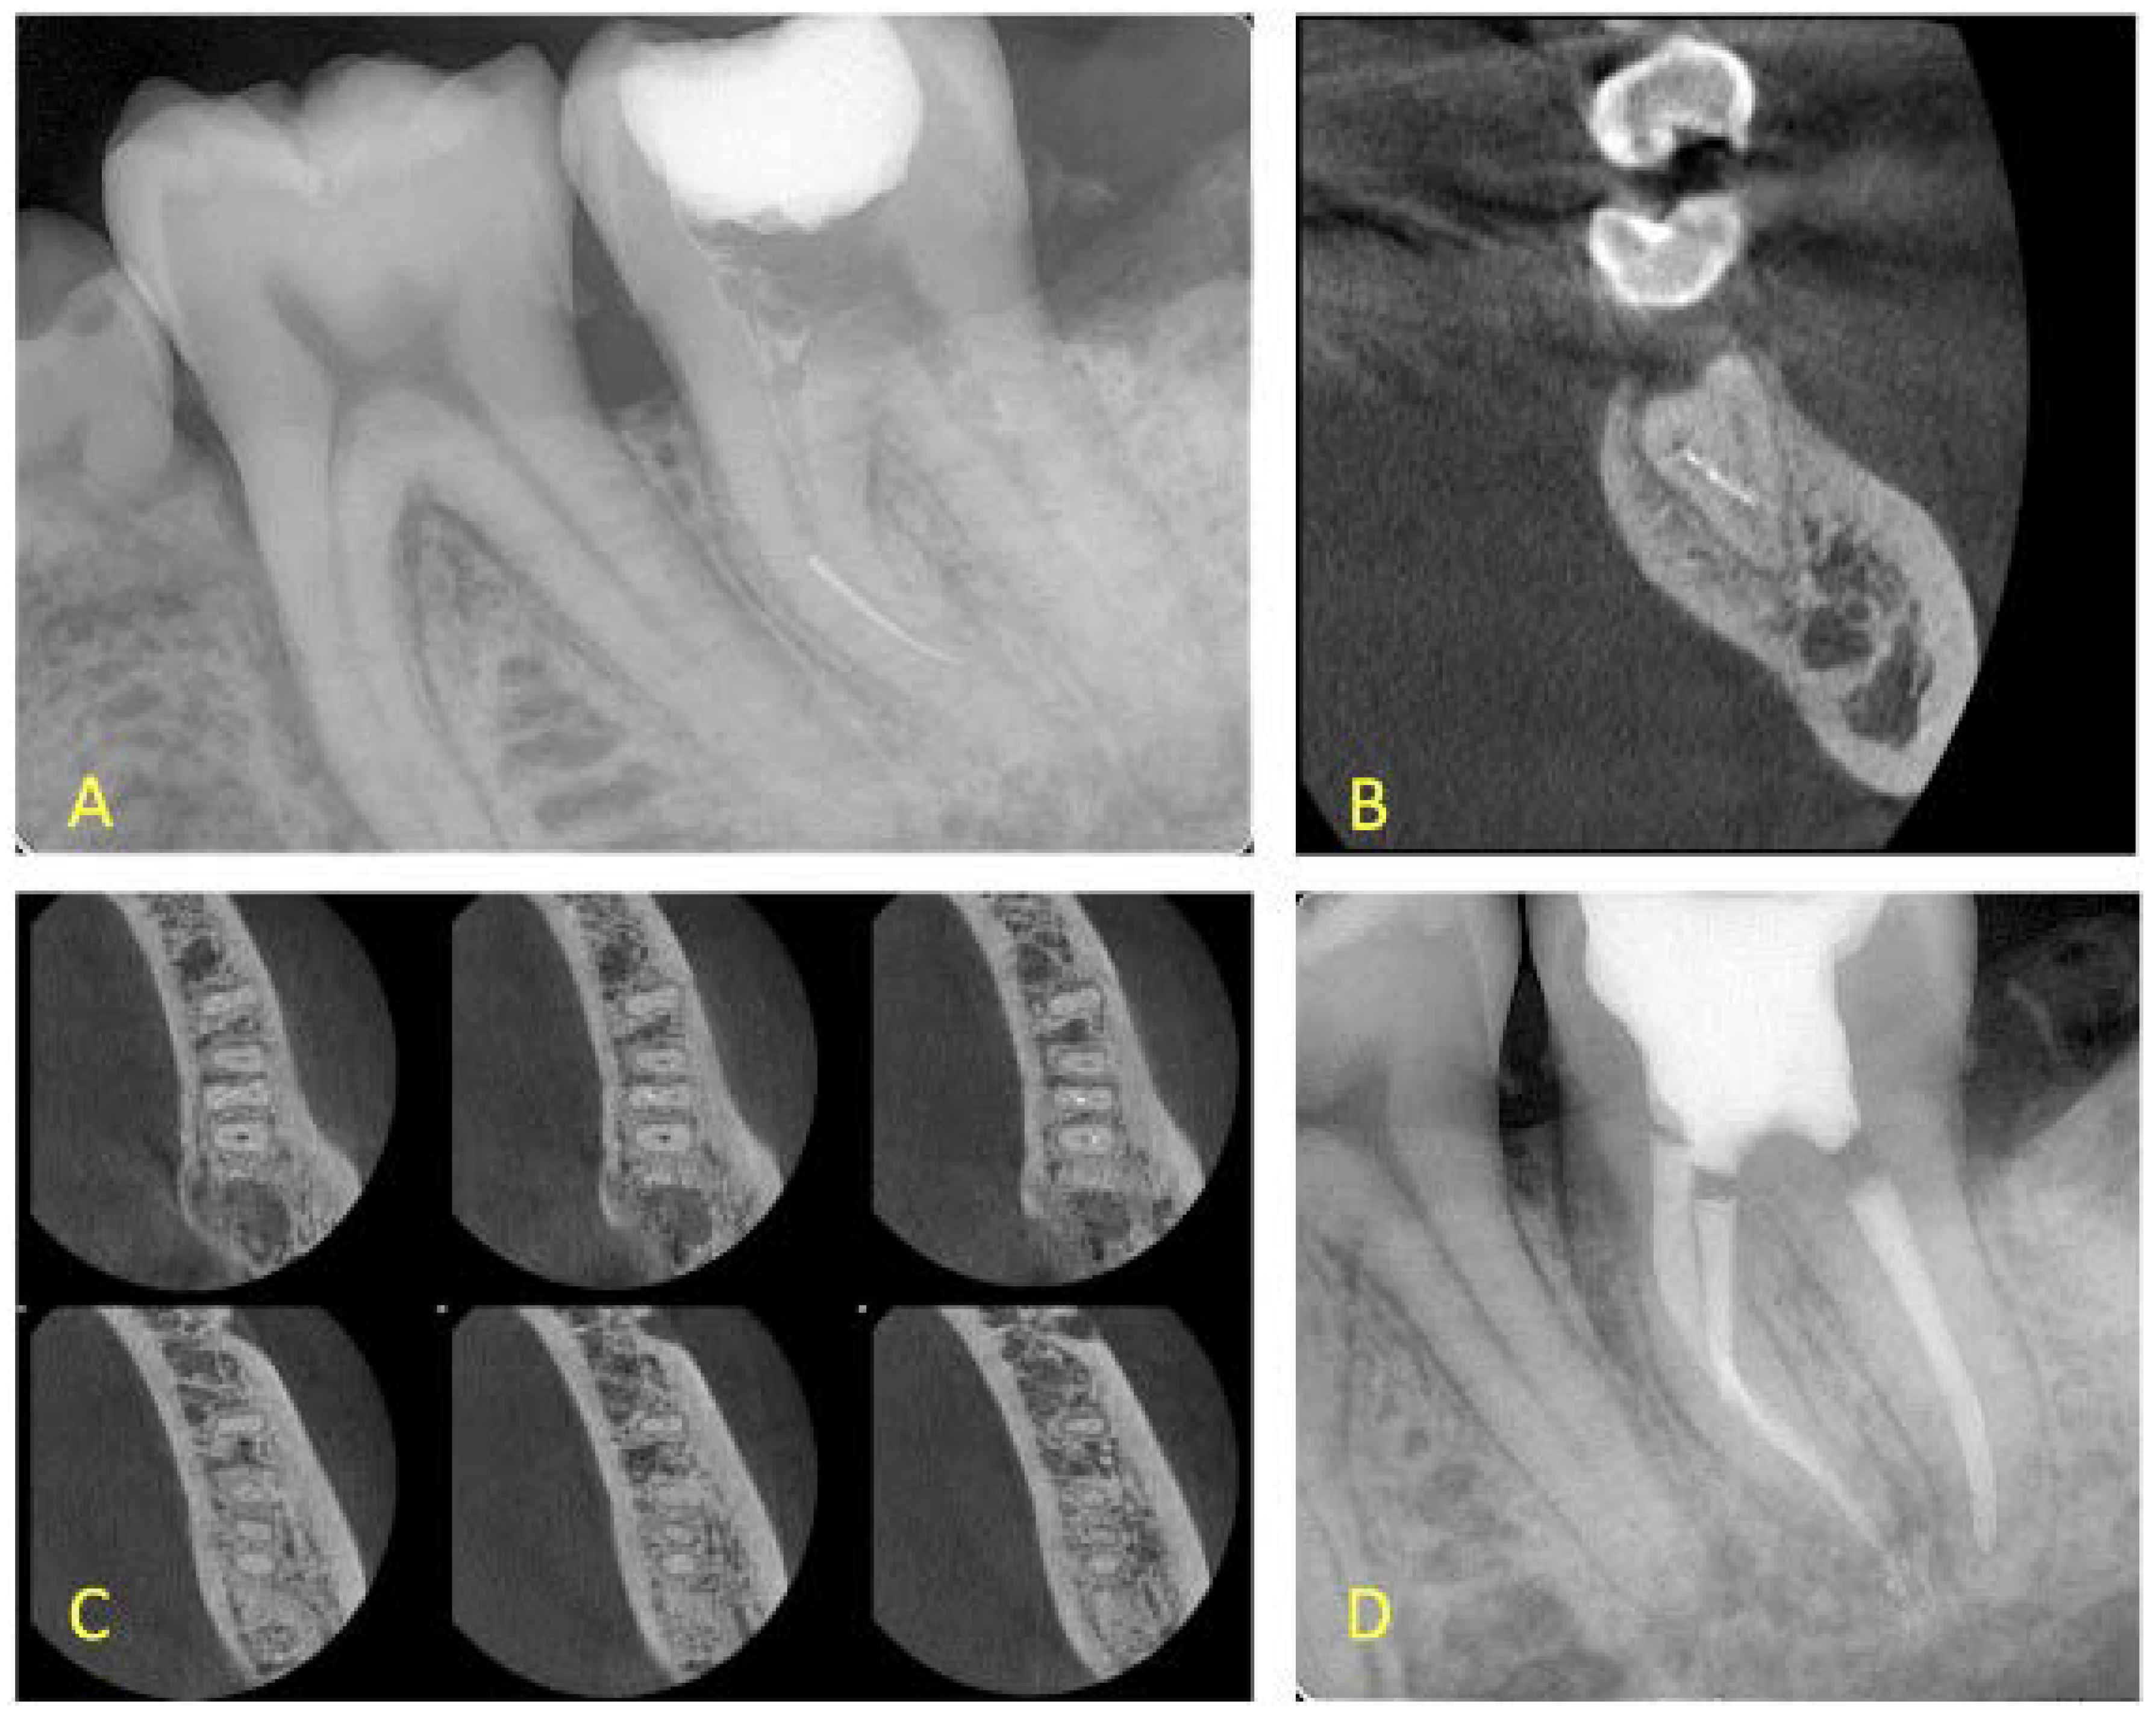

- In cases where the canals were merging, then a final treatment plan of leaving the fragment in situ was set, irrespective of the presence or absence of lesions (Figure 3 and Figure 4). The only occasion that would induce a modification to this treatment plan (i.e., leave the fragment in situ) was to conclude, after CBCT assessment and evaluation of canal curvature, that the removal of the fragment located at the middle level of the root would not be of a high difficulty degree procedure (Figure 5).